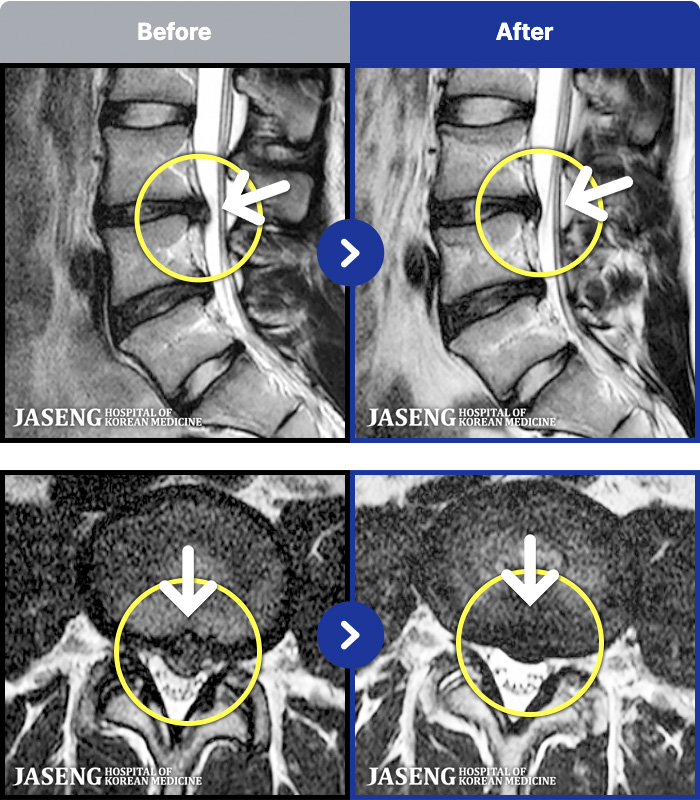

MRI ġ

1,301 MRI ũ ʸ Ȯϼ.